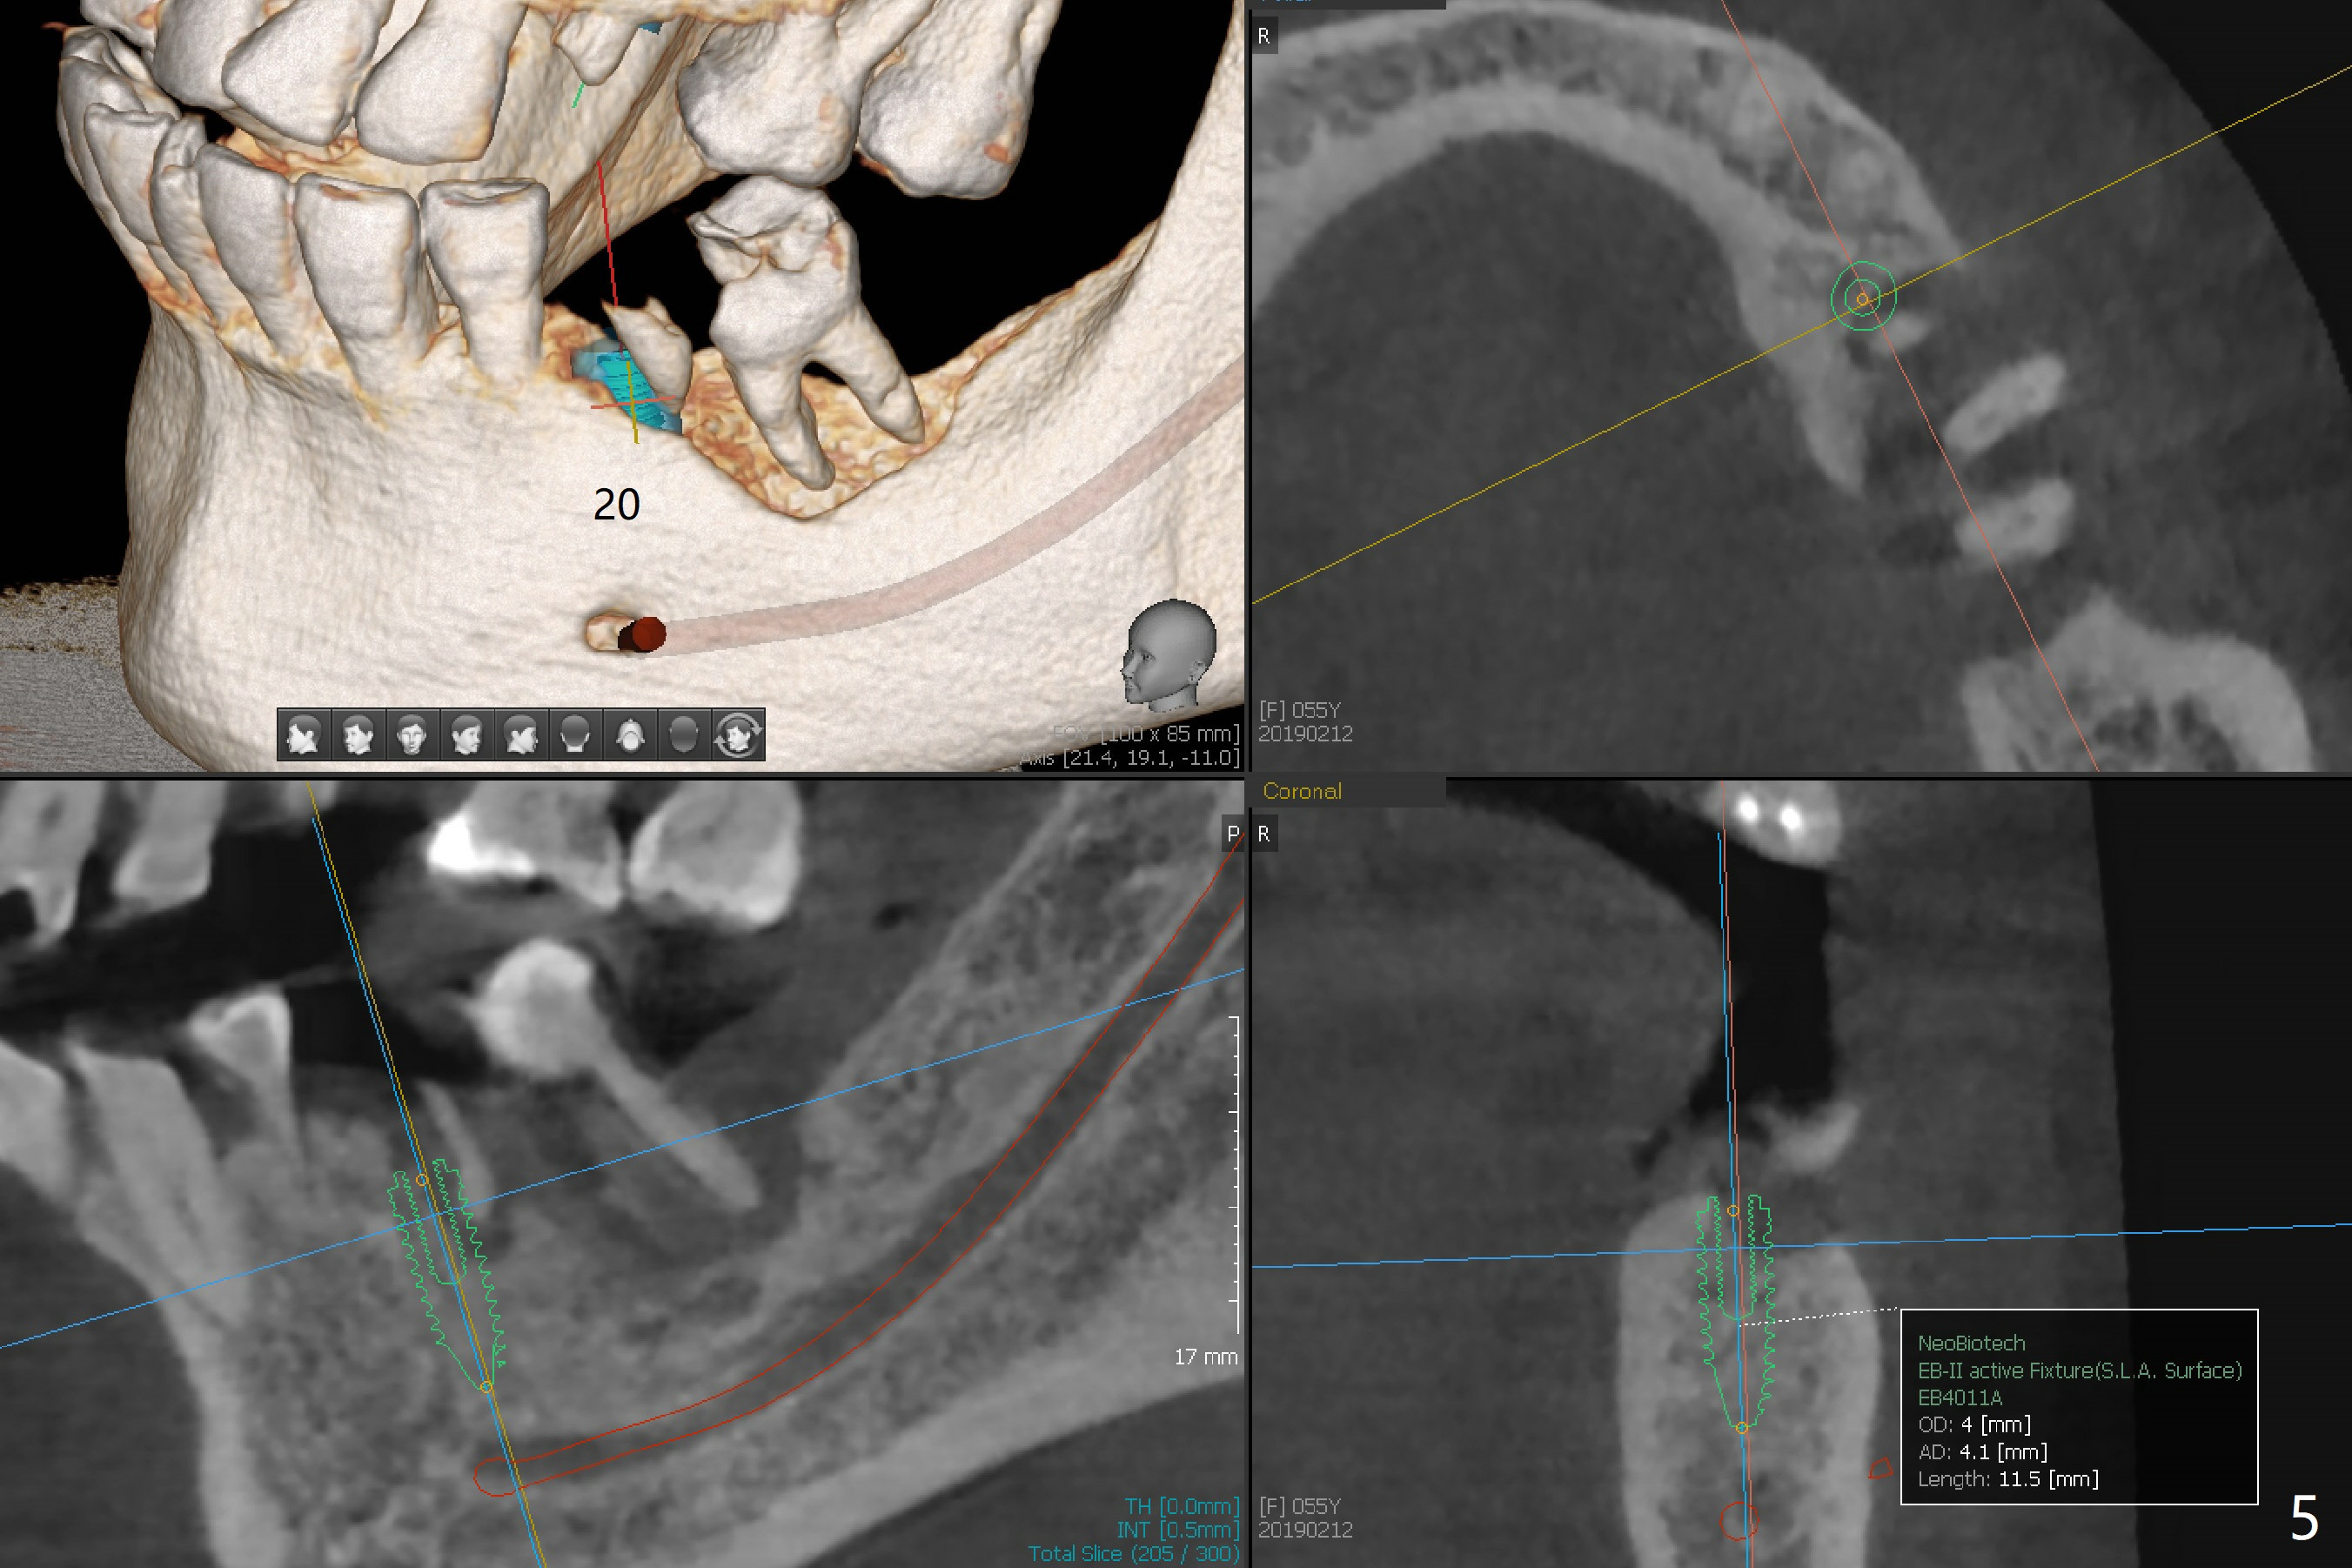

A 55-year-old woman has poor dentition, which is partially related to her previous history of ice chewing (Fig.1). The long bone height in the jaws suggests bruxism and requires as many teeth and implants as possible. After SRP, caries will be removed from #14 and 15 for determination of salvageability (Fig.2). The patient prefers to save the tooth #30. Endo referral will be recommended for #14 and 30. If the tooth #14 proves to be nonsalavageable, it will be extracted with #12 for immediate implants and subsequent FPD (Fig.3,4). Immediate implant will be avoided at #19 due to severe bone loss. Instead a short implant (5.5x5 or 6 mm) will be placed at #18, while a 4x11.5 mm one at #20 for FPD (Fig.5,6). All of the implant will use guides. There is a special point at #18. After use of 4.5 mm drill, the guide will be removed for free hand osteotomy using 5.0 mm drill, 5.5 mm tap and implant placement. PRF will be prepared for membrane and sticky bone at #19 and 20. For the lower right quadrant, treatment for #30 should be conducted first, either RCT or implant. The tooth #29 will be uprighted using #30 as an anchor, if the former is salvageable. The implant at #28 will be placed last (Fig.7,8).